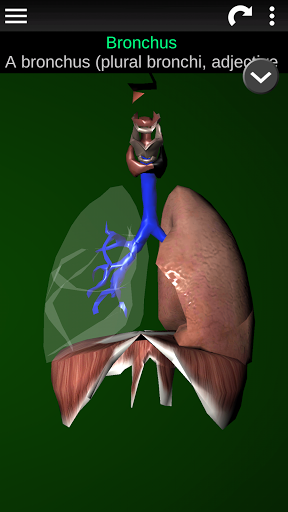

* Дихальна система, яка включає трахею, бронхи, легені та анімацію цієї системи.

* Описи кожного органу.